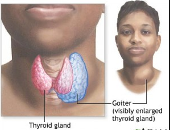

chemotherapy treatments for cancer and medical conditions such as

thyroid problems or diabetes. Other factors may also play a role in the

₦48,000.00Goiter - Treat Enlargement of the Thyroid Gland in the Neck.